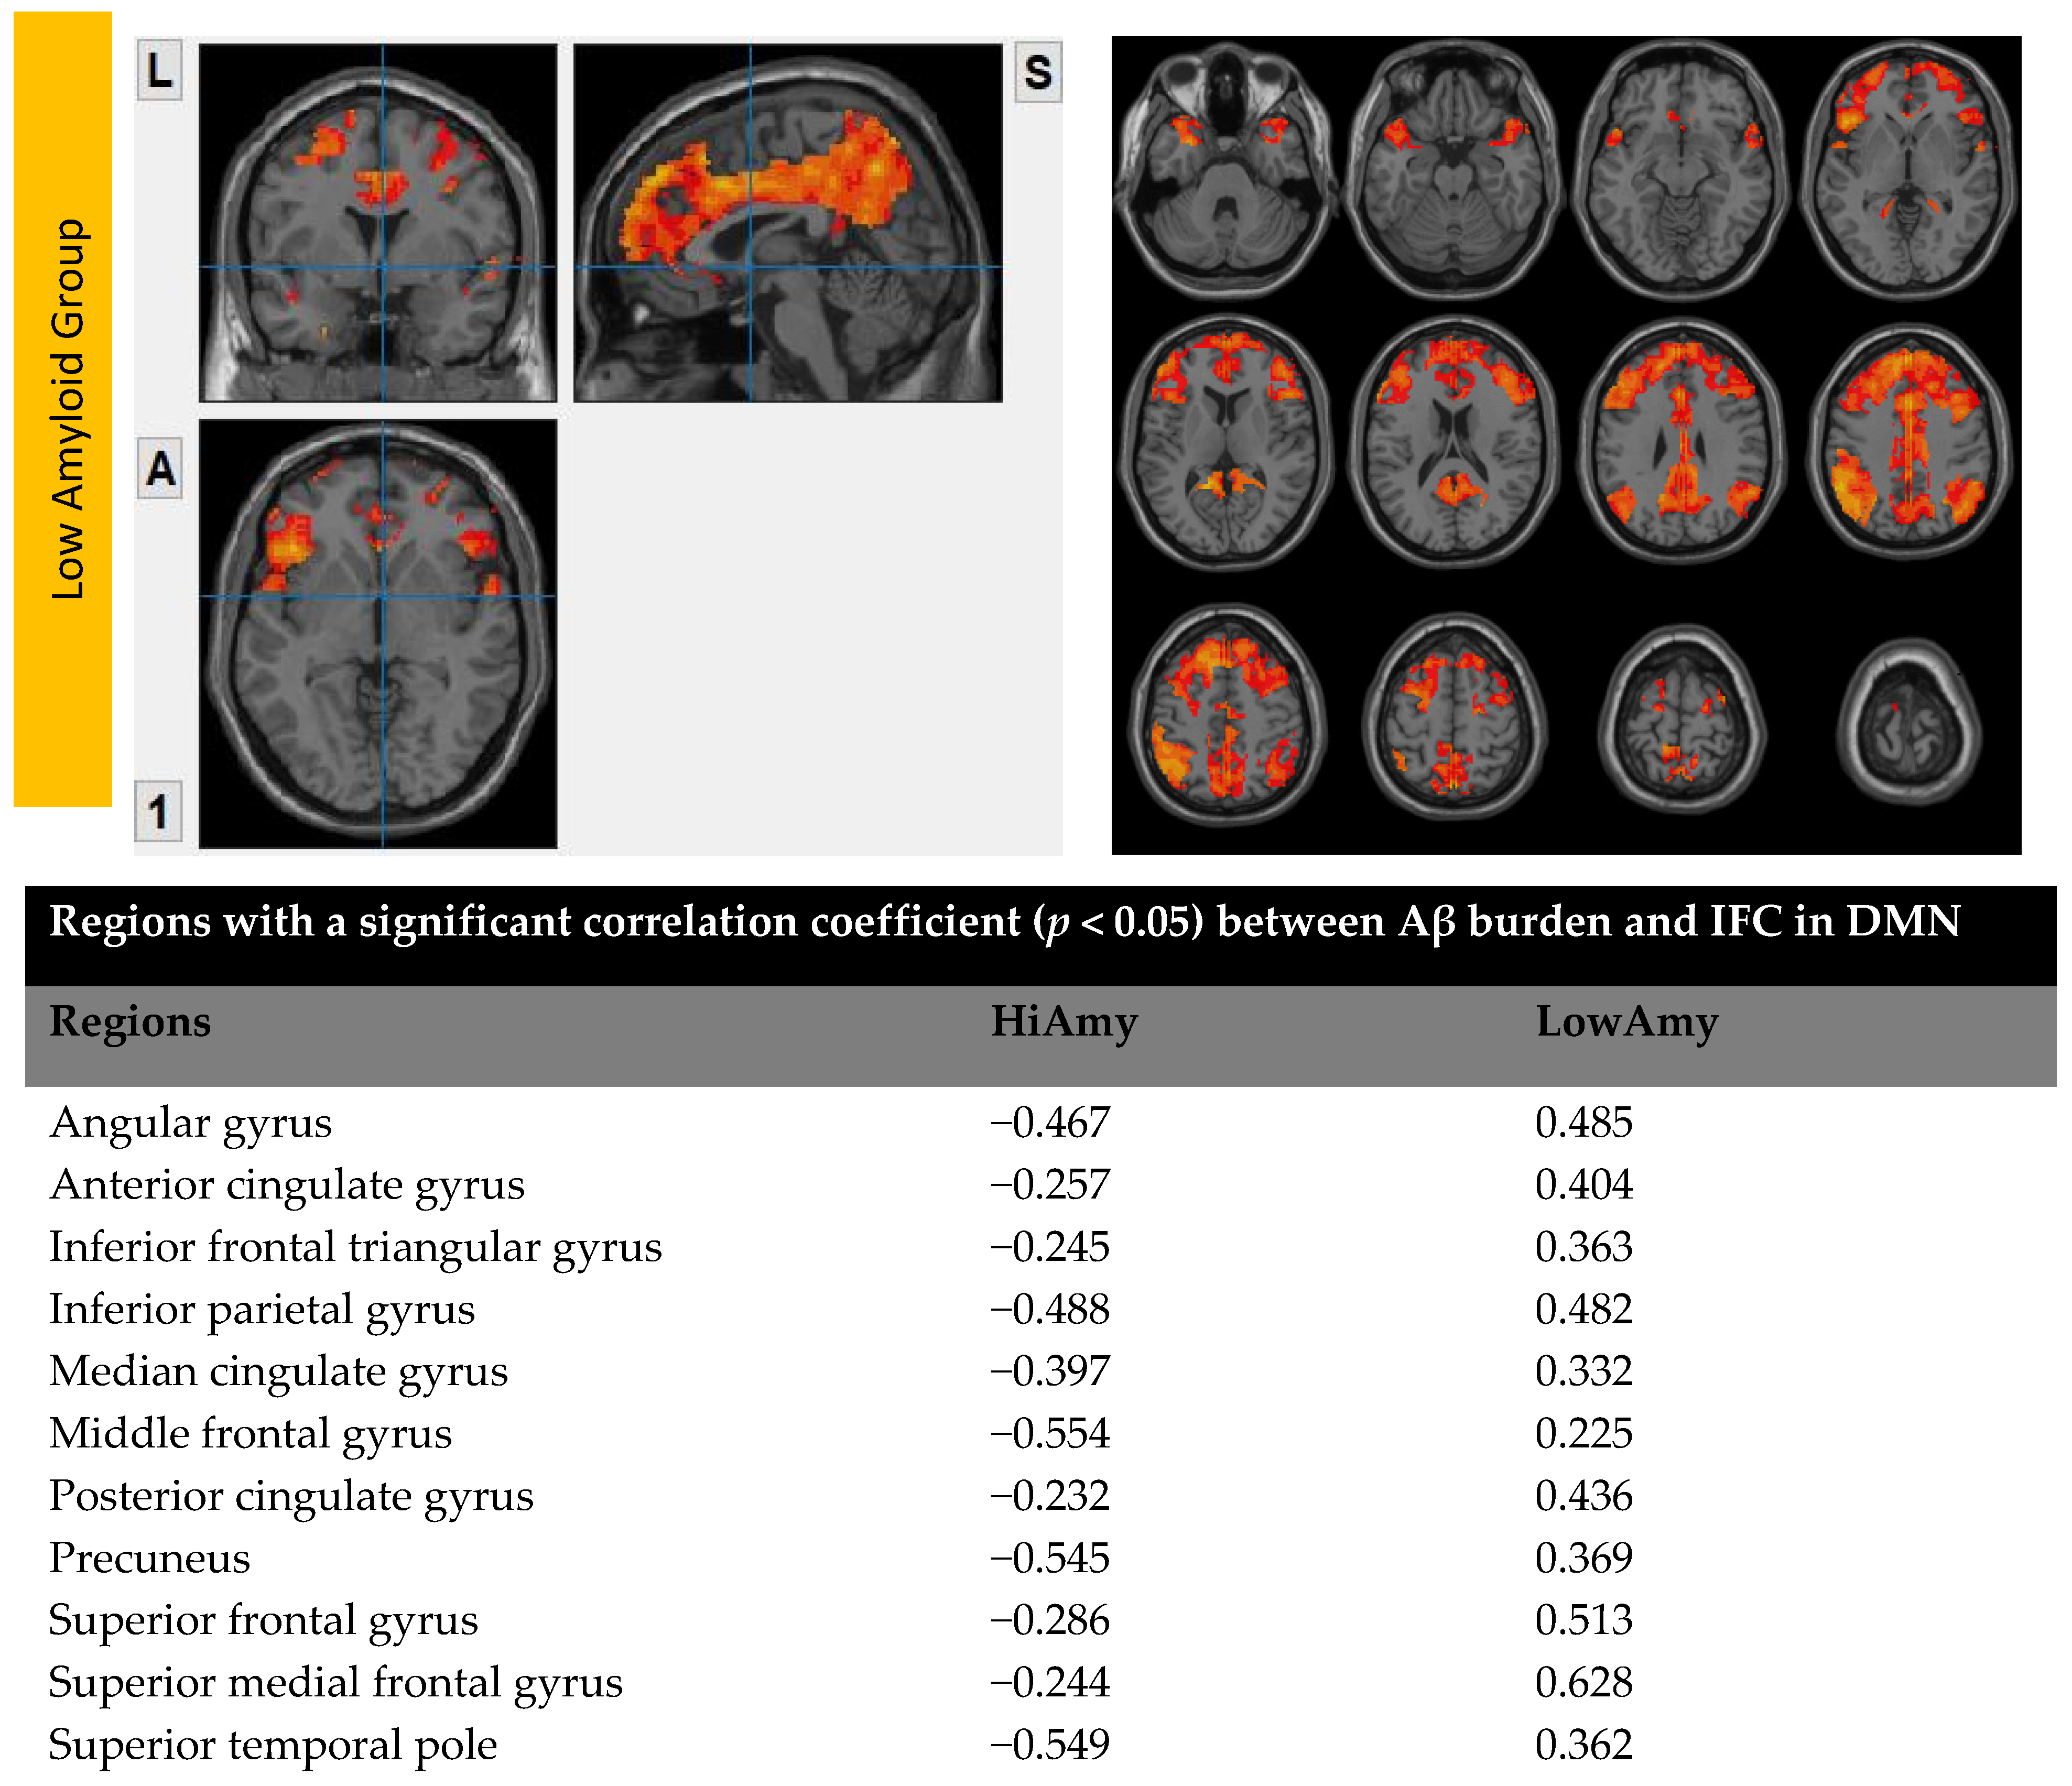

6.3. Interhemispheric Functional Connectivity (VMHC) Maps

7.2. Within CEN